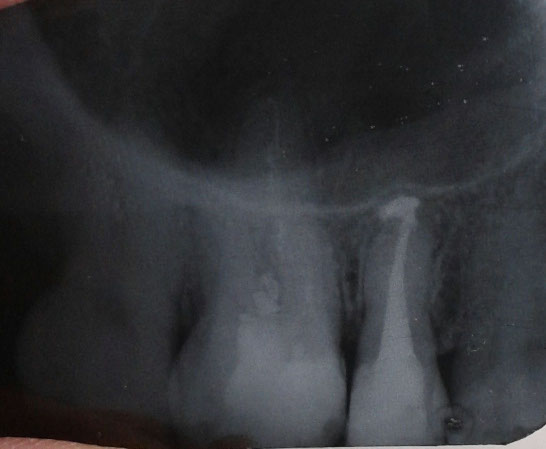

Сейчас десна между пятым и шестым зубом воспалилась, покраснения и припухлости больше у пятерки, к тому же там десна у самого зуба еще и потемнела. И как будто лунка от гнойника. Покраснение вдоль корня к нёбу. Какой из этих зубов дает о себе знать? Может ли воспаление шестого зуба распространиться на пятерку? Или пятерка сама вызывает воспаление? Рентген-снимок, сделанный в декабре: у 5-ки (справа крайний) материал заполнителя вышел за пределы корня. Это нормально? У 6-ки, как видно, канал корня зуба не заполнен, т.е., выходит, не залечен? Могла ли врач «забыть» залечить третий корень шестерки? И что это за два "предмета" в середине канала шестого зуба?

Добрый день, уважаемый пациент. Причиной вашего беспокойства может быть любой из этих зубов, так как на верхушке пятого зуба наблюдается значительное количество материала, что крайне не допустимо, и, также, воспаление. То же самое у шестого зуба, имеется воспалительный процесс. и причина - некачественное лечение каналов. Рекомендую вам не тянуть, так как воспалительный процесс и грануляция имеют свойства распространяться. И вообще, ходить постоянно с таким состоянием нельзя, вы просто рискуете потерять несколько зубов. Рекомендую неотлагательно обратиться к врачу и, желательно, к другому.